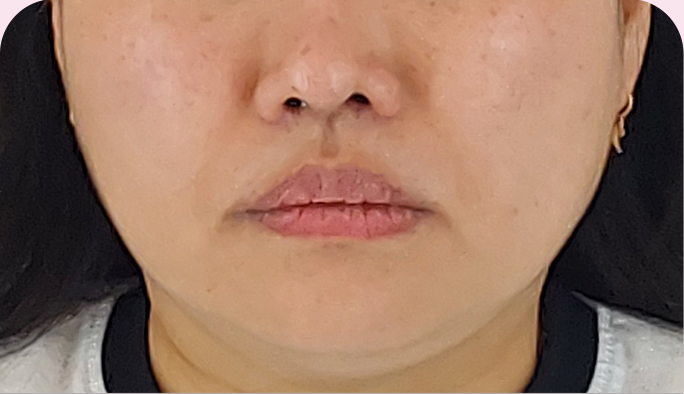

스킨부스터와 실리프팅의 장점만 합쳤다!

Collagen

Rejuvenating콜라겐 채움실

다량의 콜라겐실을 삽입해,

잔주름은 지우고 탄력을 채워 강력한

피부퍼밍 효과를 만드는 채움실 리프팅

실은 리프팅만 가능?

사‘실’은 당기기만 하진 않아요!

당기는 ‘실’과 채우는 ‘실’의 차이

PDO 성분의 실은 각종 인체 수술에서 내부 장기의 봉합에 광범위하게

사용되어 온지가 수십년이 넘은 안정성이 이미 확립된 소재입니다.

코그 형태의 물리적 리프팅 뿐 아니라

피부 및 조직 내 시술 할 경우

콜라겐 형성(탄력 증가),

진피 내 혈관 형성 촉진 등의 부수적인 효과가

시술 후 최대 48주까지

장기적으로 지속되는 것으로

다수의 의학 논문으로

입증되었습니다.